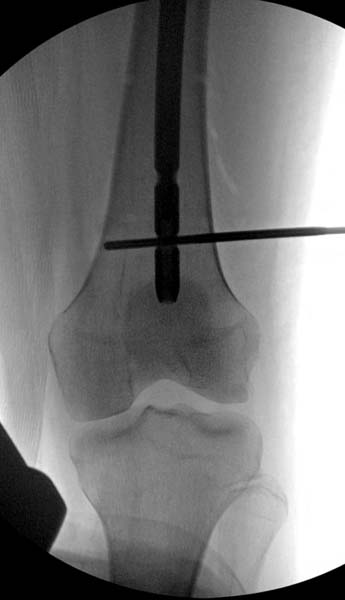

> Больная стабильная после хирургических мероприятии и получив добро,

> приступили к закрытому вправлению таранной кости с укладкой наружного

> фиксатора. Затем укладка больную на бок и открытый остеосинтез